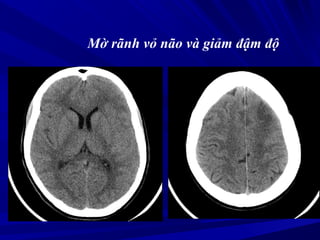

Mờ Khe Sylvius

Khe Sylvius

Không thấy

Mờ rãnh vỏ não và giảm đậm độ